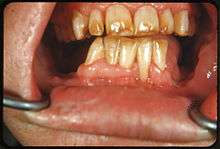

Tooth discoloration (also termed tooth staining) is abnormal tooth color, hue or translucency.[1] External discoloration is accumulation of stains on the tooth surface. Internal discoloration is due to absorption of pigment particles into tooth structure.[2][3] Sometimes there are several different co-existent factors responsible for discoloration.[4]

Extrinsic discoloration

Extrinsic discolorations are common and have many different causes.[11] The same range of factors are capable of staining the surface of restorations (e.g., composite fillings, porcelain crowns).[11] Some extrinsic discolorations that are allowed to remain for a long time may become intrinsic.[10]

- Dental plaque: Although usually virtually invisible on the tooth surface, plaque may become stained by chromogenic bacteria such as Actinomyces species.[12]

- Calculus: Neglected plaque eventually calcifies, and leads to formation of a hard deposit on the teeth, especially around the gumline. The color of calculus varies, and may be grey, yellow, black or brown.[12]

- Tobacco: Tar in smoke from tobacco products (and also smokeless tobacco products) tends to form a yellow-brown-black stain around the necks of the teeth above the gumline.[12]